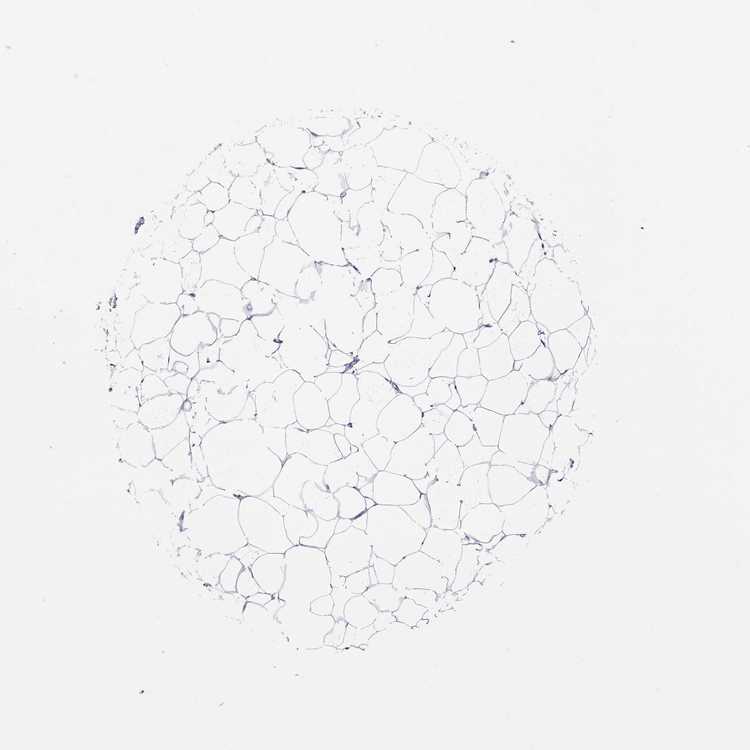

BREAST - Antibody stainingi

Antibody staining in the annotated cell types in the current human tissue is reported as not detected, low, medium, or high, based on conventional immunohistochemistry profiling in selected tissues. This score is based on the combination of the staining intensity and fraction of stained cells.

Each image is clickable and will lead to virtual microscopy that enables deeper exploration of all samples and also displays staining intensity scores, fraction scores and subcellular localization as well as patient and tissue information for each sample.

Antibody HPA075172

Adipocytes Not detected

Glandular cells Not detected

Myoepithelial cells Not detected